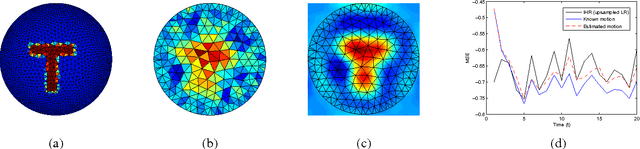

Super-Resolution Reconstruction of Electrical Impedance Tomography Images

Abstract:Electrical Impedance Tomography (EIT) systems are becoming popular because they present several advantages over competing systems. However, EIT leads to images with very low resolution. Moreover, the nonuniform sampling characteristic of EIT precludes the straightforward application of traditional image ruper-resolution techniques. In this work, we propose a resampling based Super-Resolution method for EIT image quality improvement. Preliminary results show that the proposed technique can lead to substantial improvements in EIT image resolution, making it more competitive with other technologies.